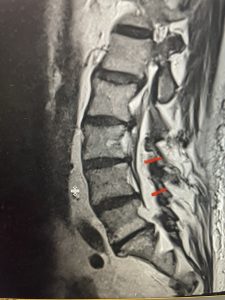

This 66 year-old male with Factor XI deficiency had originally had a decompressive laminectomy L2-S1 and in situ fusion about three years prior for severe thecal sac compression mainly due to severe epidural lipomatosis (Fig 4).

(Fig 4a) Sagittal (a) and Axial (b) T2-weighted lumbar MRI demonstrating severe spinal stenosis L2-5 (arrow)and extruded disc at L3-4 on axial image (arrow)

(Fig 4b)